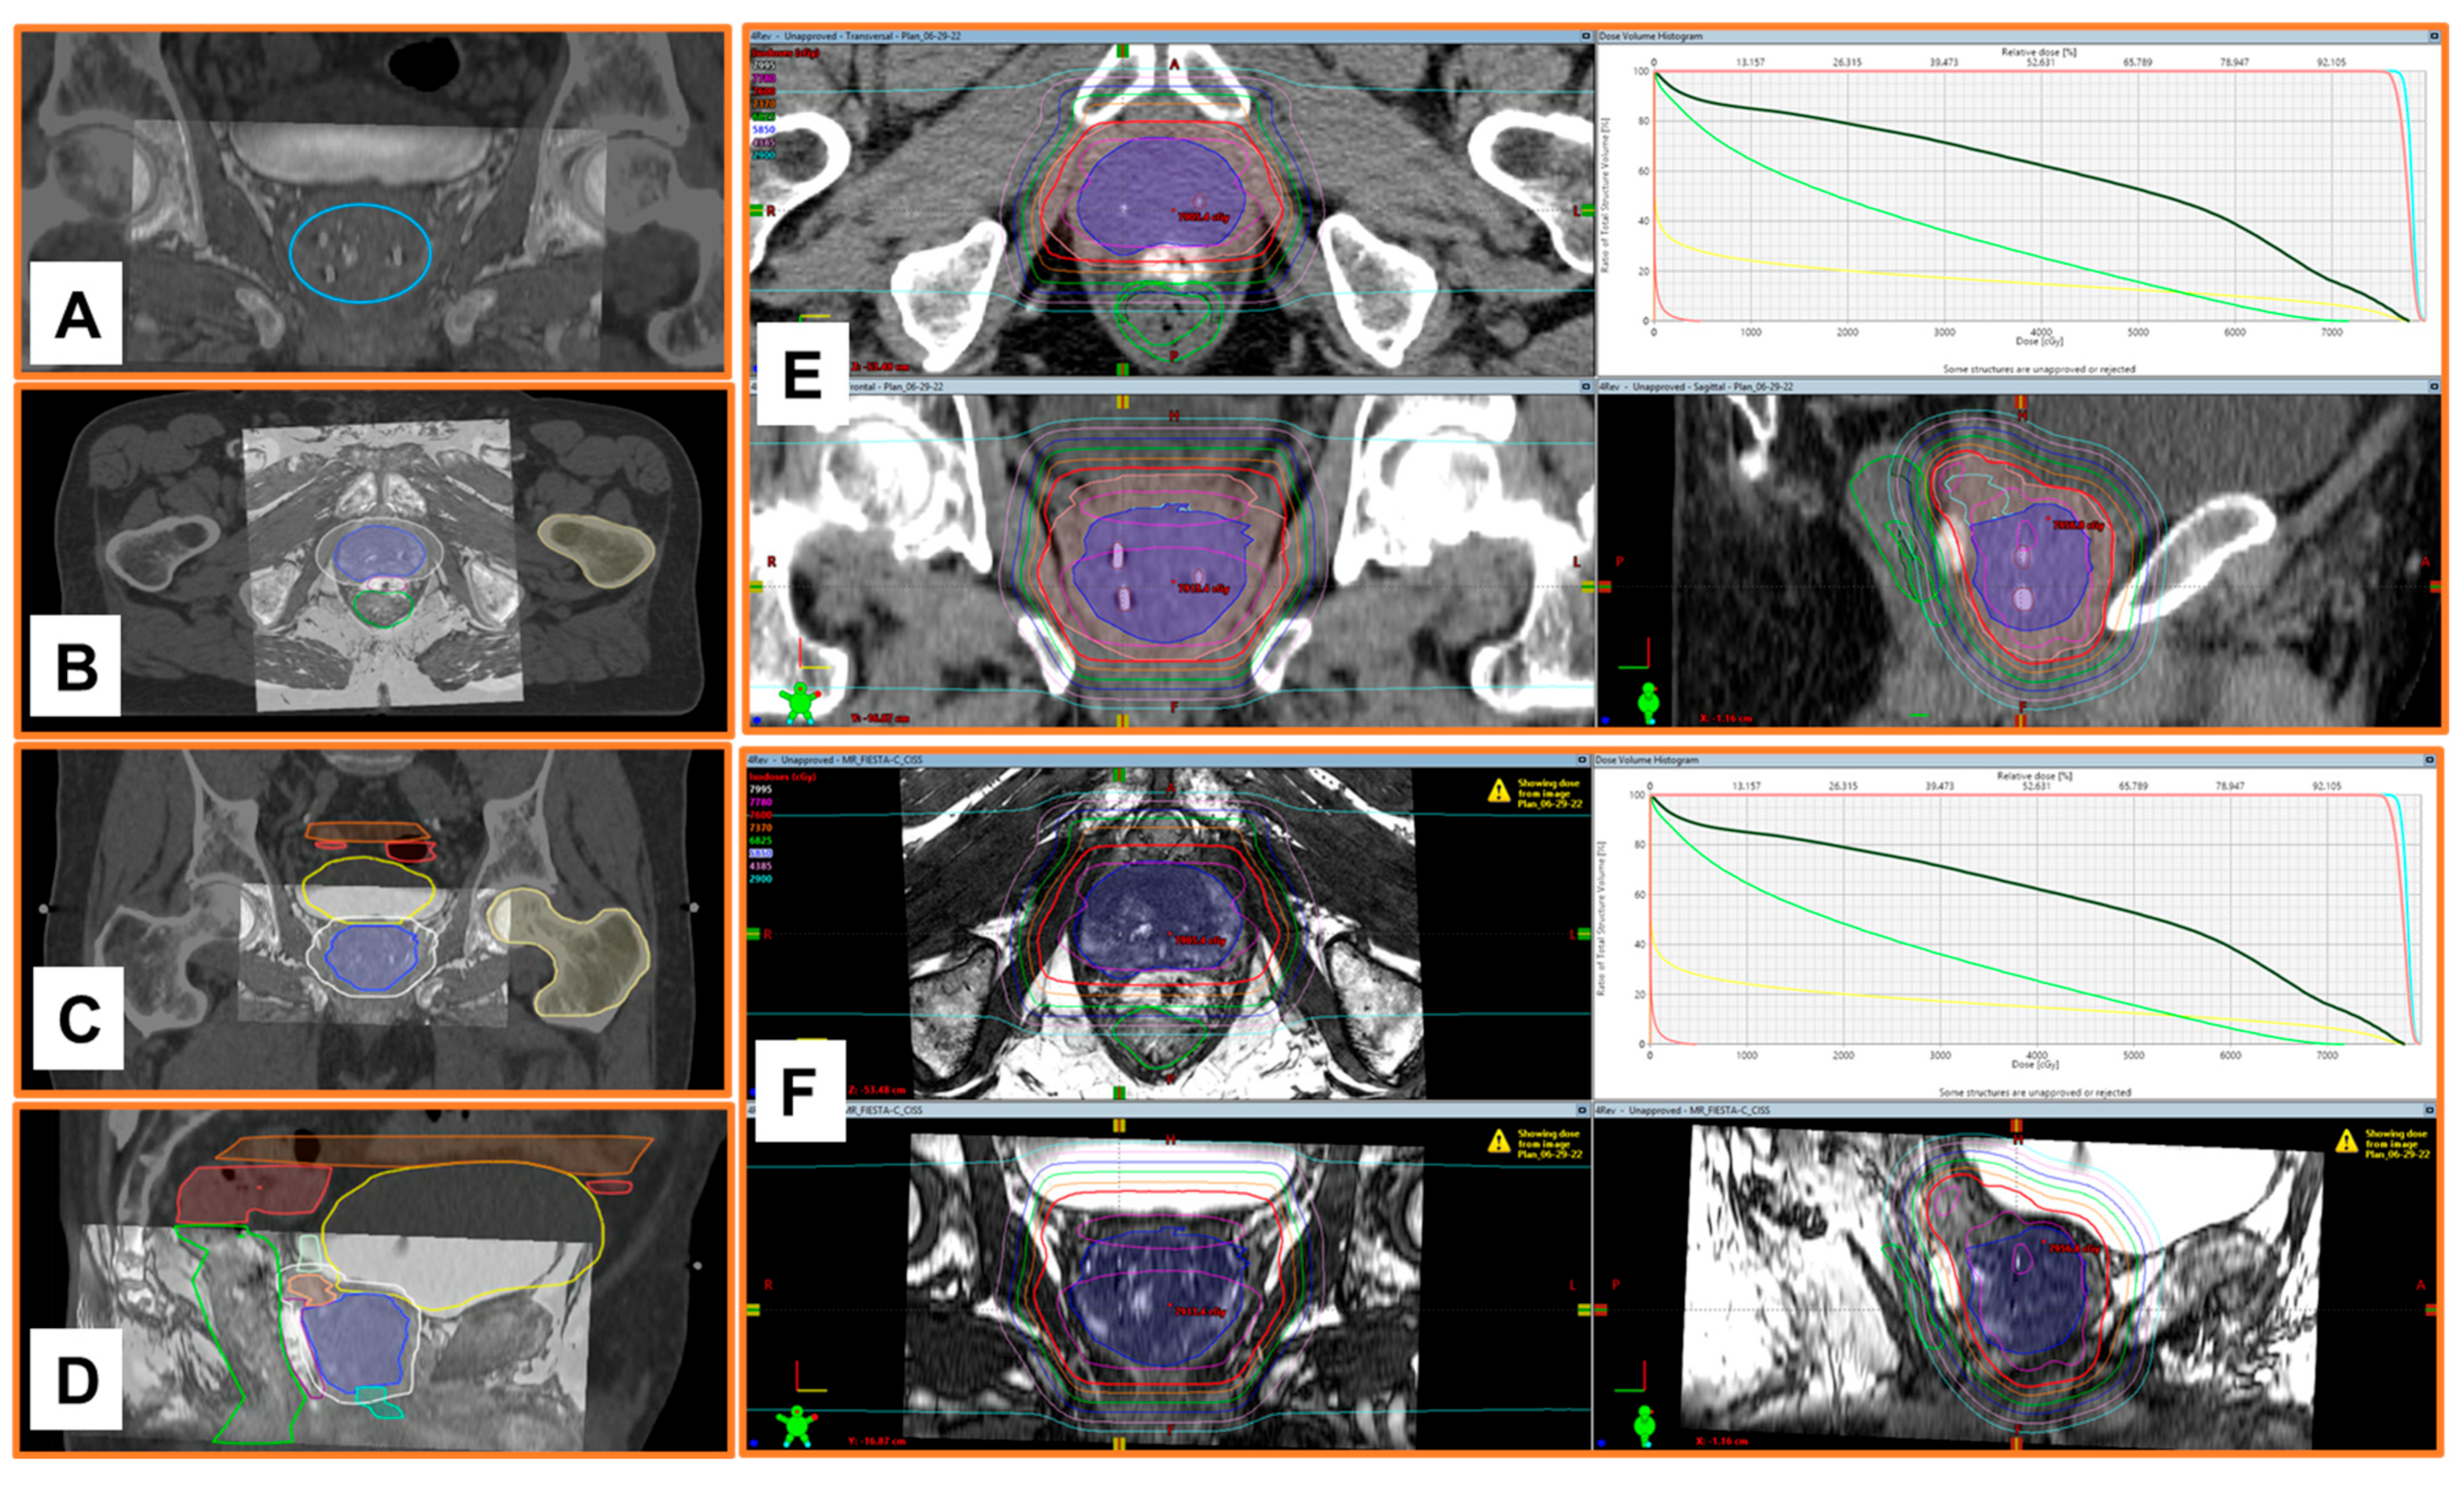

3.4. Visibility of NOVA Markers in a Clinical Case